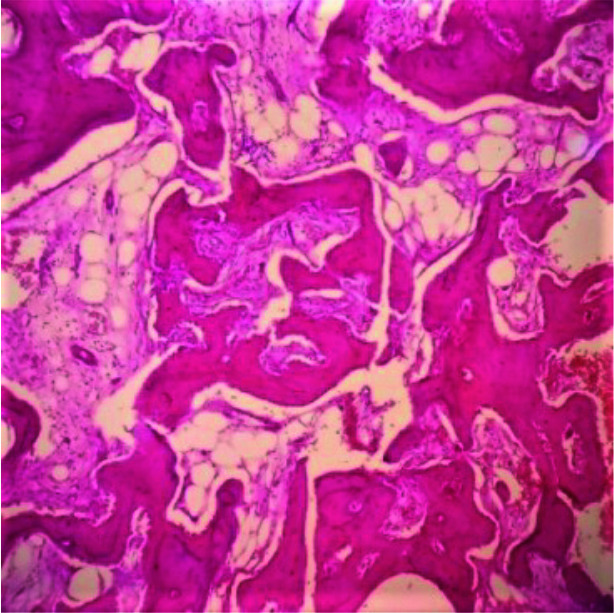

Materials and method: This was a retrospective study where hematoxylin and eosin (H&E) slides and archival records of fibrous dysplasia (FD) and ossifying fibroma (OF) cases were reviewed. The sections were assessed for permeation of marrow spaces, stromal growth pattern, cytologic atypia, mitotic activity, and pattern of bone growth, which are parameters for diagnosing LGCOS. The predictive histologic index of malignancy (PHIM) was determined by a sum of the scores and graded as 0=nil, 1=low, 2 & 3=moderate, and 4 & 5=high. Data were presented using descriptive analysis.

Results: Ninety-three cases of FLs met the inclusion criteria, consisting of 40(43%) cases of FD and 53(57%) cases of OF. The peak age of presentation for FD and OF was 2nd and 3rd decade. There was a female preponderance of 1:1.6. The maxilla was the most common site affected by FD, while the mandible was most commonly affected by OF. For FD cases, the PHIM was moderate in 10(25%) cases and low in 21(52.5%) cases. Similarly, for OF cases, 30(56.6%) cases had low grade PHIM while 10(17%) cases had moderate grade PHIM.